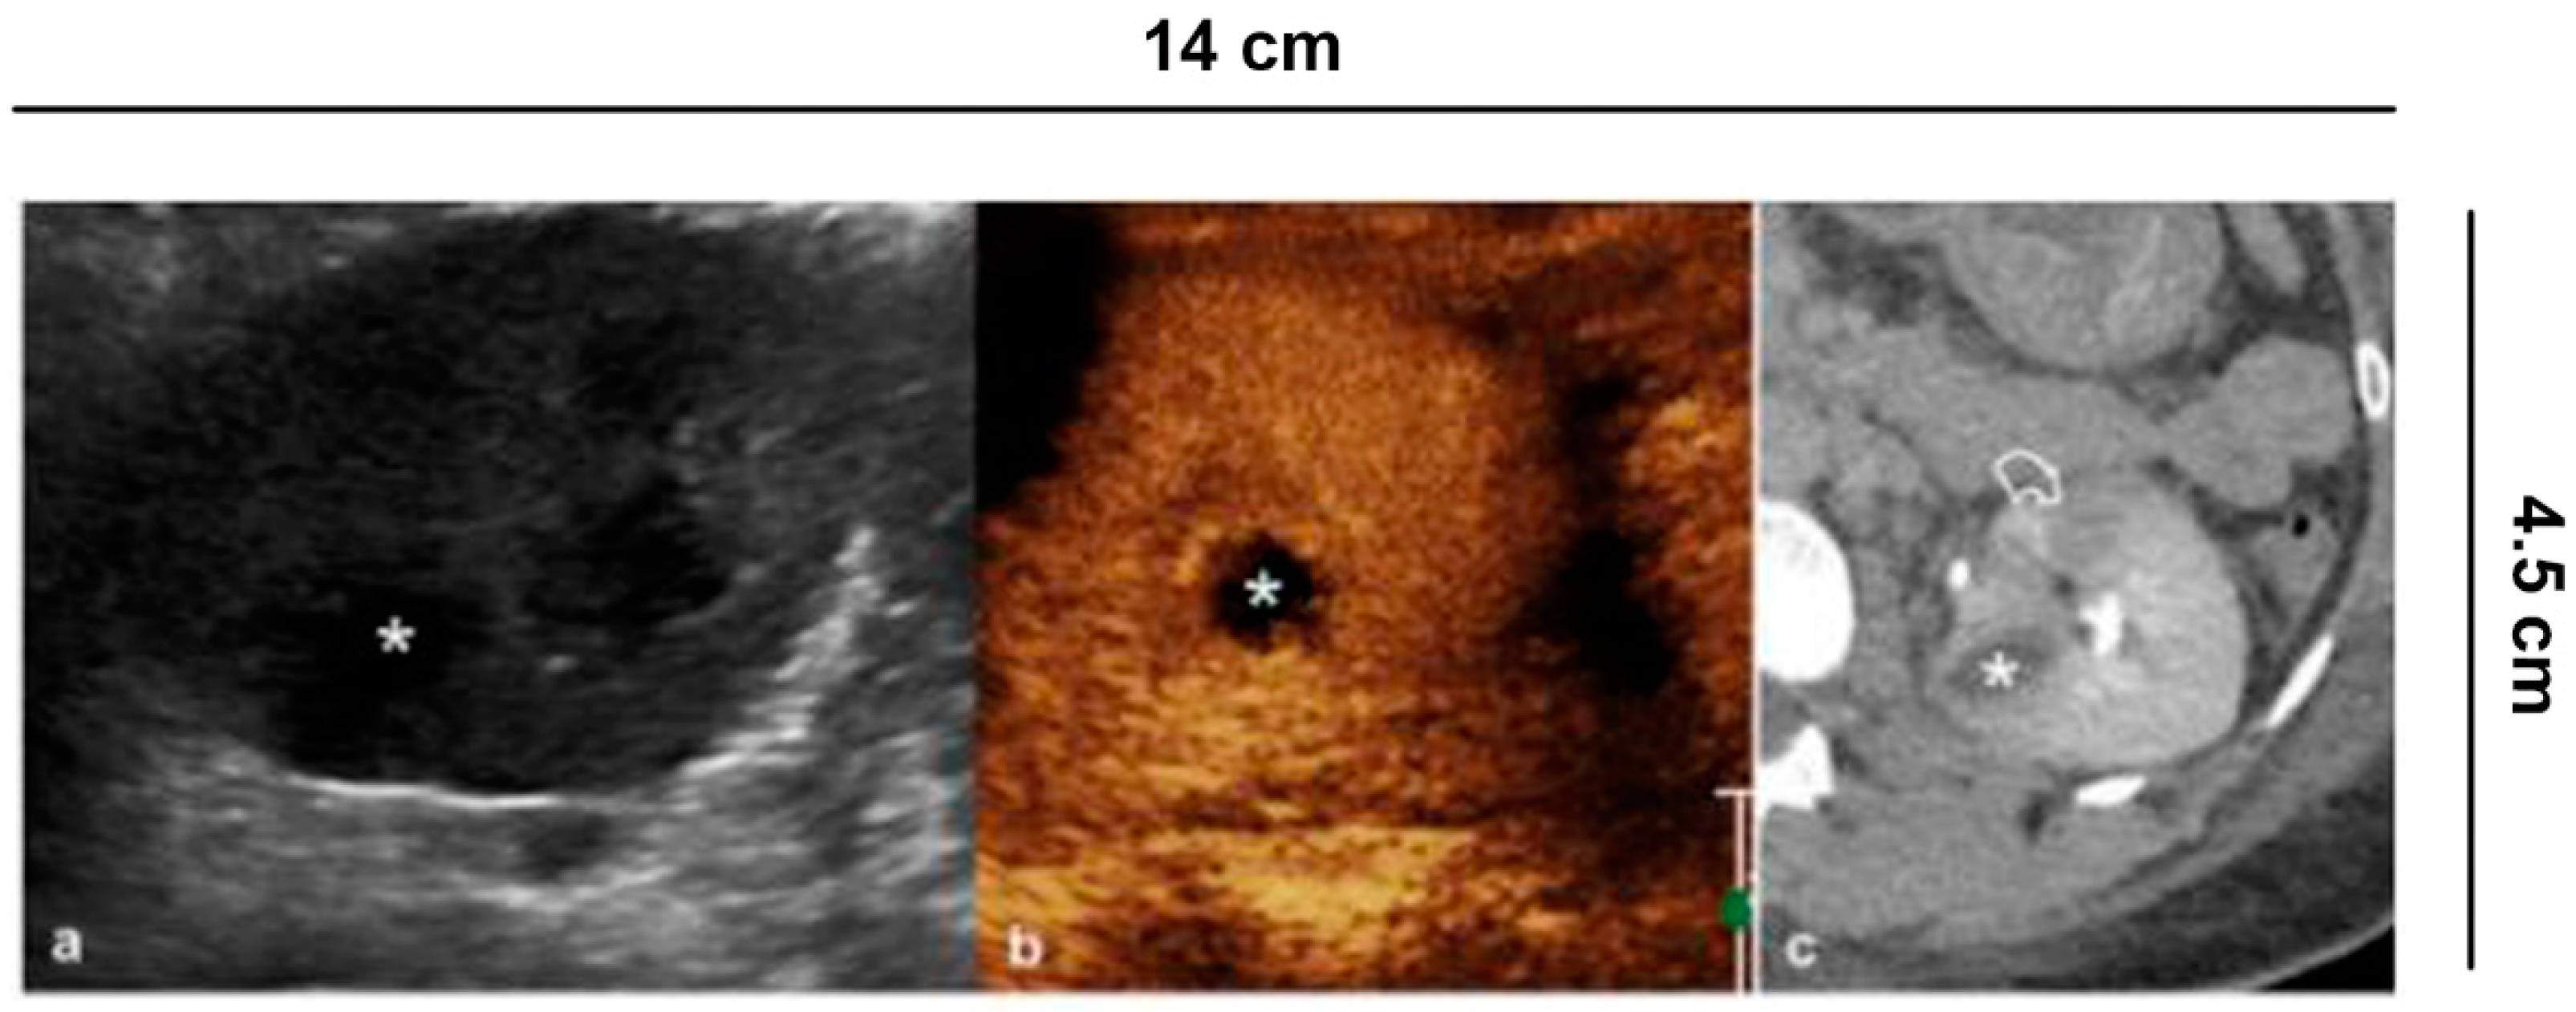

6.6. Complicated Pyelonephritis

Pyelonephritis is a clinical diagnosis. Ultrasound is required to rule out obstructive causes. Other imaging such as CEUS or CECT are indicated in complicated pyelonephritis, or if clinical improvement is lacking at 72 h after medical treatment with antibiotics [] (Figure 7). Ultrasound is not specific, and can be completely negative. Conversely, CEUS can visualize hypo-perfused areas of parenchyma up to true avascular, rounded areas, with possible peripheral rim, consistent with abscesses. Inflammatory areas are more visible in the parenchymal late phase []. In complicated pyelonephritis, CEUS can be used as a monitoring tool for therapeutic response.

Figure 7.

Complicated pyelonephritis. 53 year-old-woman with left flank pain and fever. (a) B-mode US appreciates inhomogeneous, hypoechoic area (asterisk); (b) CEUS performed in the same session confirms the presence of an avascular lesion with a peripheral rim, consistent with abscess (asterisk); (c) Urographic phase CECT, performed for the clinical worsening of the patient, confirms the presence of abscess (asterisk) and hypo-perfused area (curved arrow) at the lower pole of the kidney.